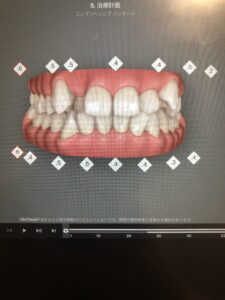

私のもともとの歯並びがこちらです。